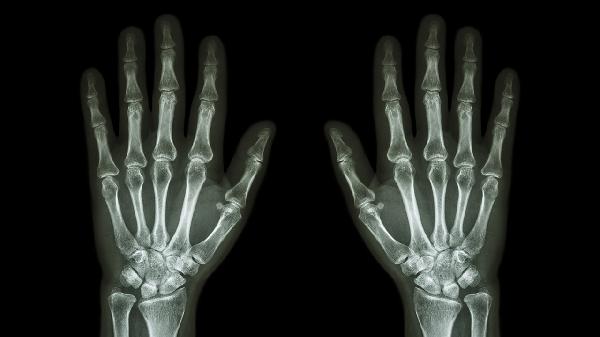

多个手指关节疼痛是怎么回事

多个手指关节疼痛可能与骨关节炎、类风湿关节炎、痛风性关节炎、腱鞘炎、外伤等因素有关,可通过药物治疗、物理治疗、手术治疗等方式缓解。建议及时就医明确病因,在医生指导下进行针对性治疗。